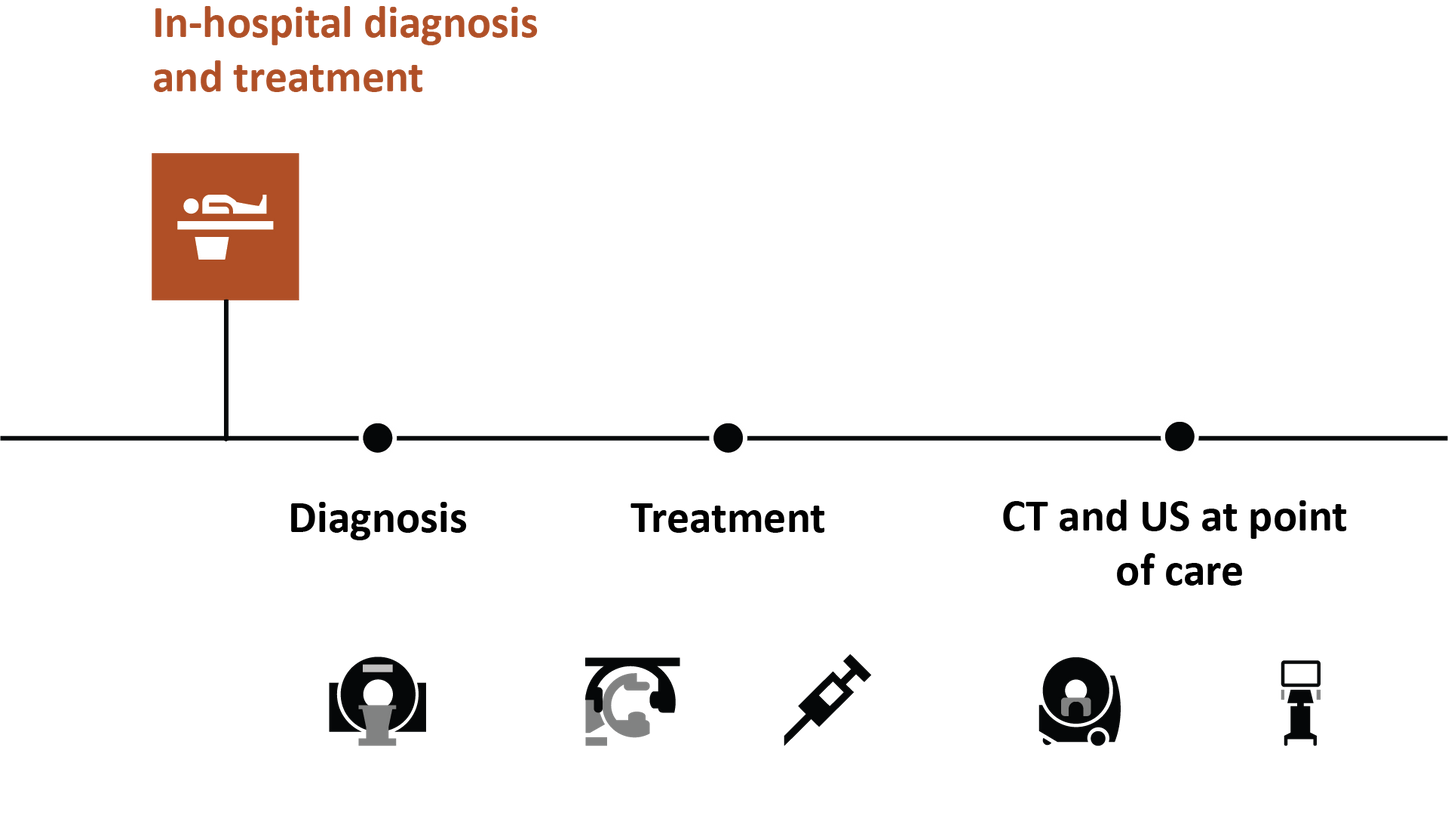

Stroke solutions

As your partner in stroke management, we keep you ahead of your time. Our advanced technologies let you speed up stroke care and transform care delivery along the entire pathway – from stroke screening and pre-hospital diagnosis and care to in-hospital diagnosis and treatment and (secondary) stroke prevention to follow-up imaging. Explore our offerings for stroke care!

Clear image quality for confident diagnosis and treatment

To quickly and confidently diagnose stroke, assess its impact, and perform mechanical thrombectomy, you need clear information. All our CT and MRI scanners as well as angiography systems let you see even small anatomical details in excellent quality. See for yourself!*

In recent years, various clinical trials have shown the advantages of performing endovascular thrombectomy in patients with a high stroke score as well as of one-stop stroke care.

In their study, M. Psychogios et al. have shown that diagnosing and treating potential LVO patients on one system can save valuable time and significantly improve functional outcome.6